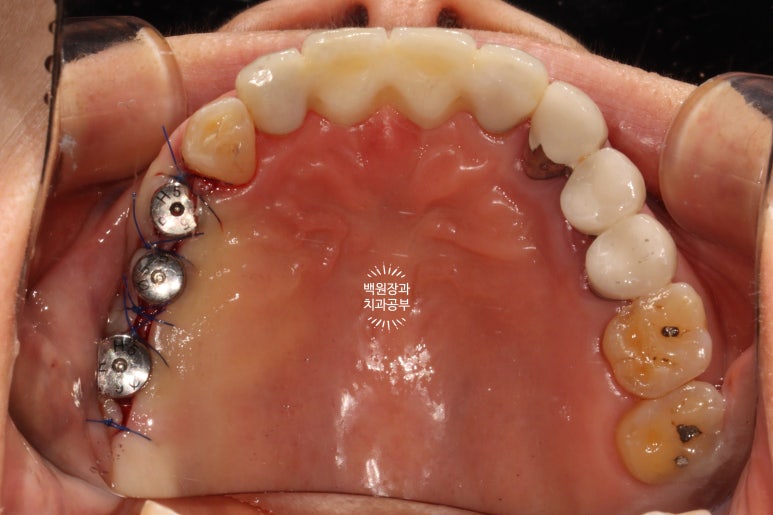

꽤나 깔끔하게 꿰매진 것을 보실 수 있을겁니다 :)

1주일이 지나 실밥을 제거한 뒤의 소견입니다.

아주 당연하지만, 이와 임플란트를 뽑으면 그 자리에 잇몸이 없으니 구멍이 나 있을 수 밖에 없겠죠?

그 구멍을 통해 뼈이식재가 다 쏟아진다면 우리가 했던 치조제보존술은 아무 의미가 없겠죠.

그래서 사용하는 것이 차폐막이라는 막이고, 실밥을 제거할 때 보이는 저 흰색의 재료들이 그 차폐막입니다.

차폐막은 콜라겐으로 이루어져 있고, 덴티움사의 차폐막이 cross-linked 방식으로 제조되어 잘 흡수되지 않고 오래 버텨주기로 유명합니다.

딱 봐도 뼈이식재가 삐져나오지 않고 잘 갇혀있을 것 같은 느낌이죠?

임플란트 1차수술 후 3개월을 더 기다려 임플란트 2차수술을 합니다.

정확히는 3개월 반 정도 기다려서 임플란트 2차수술을 해드렸습니다.

이렇게 잇몸뼈 안에 있는 임플란트에 뚜껑을 끼우면 그게 임플란트 2차수술입니다.

사실 임플란트 2차수술은 이렇게 단순히 뚜껑만 껴주는 수술이 아닙니다.

대부분의 치과의사들이 임플란트 2차수술의 역할에 대해 간과하고 있는데.... 임플란트 2차수술은 임플란트 1차수술 못지 않게 중요한 수술이며, 가장 큰 역할은 앞으로 제작될 임플란트 주변의 잇몸 환경을 적절히 조성해 주는 것입니다.

이번 60대 여자 환자분의 임플란트 재수술 케이스의 경우, 임플란트를 제거하게 된 원인은 '임플란트 주위염' 이었으며 임플란트 주위염이 발생한 이유는 기존 임플란트 주변으로 칫솔질을 잘 할 수 있는 환경이 제공되지 않았기 때문입니다.

임플란트를 심으면서 잇몸의 형태를 고려해주지 않으면, 칫솔질이 어려운 임플란트 보철물이 제작되게 되고 결국 치태가 쌓이고 치석이 쌓여 임플란트 주위염으로 고생하시게 되죠....

그래서 저는 임플란트 2차수술을 하며 근단변위판막술 (apically positioned flap)을 함께 해주면서 전정성형술 (vestibular deepening)을 함께 해주어 임플란트 완성 후에 관리가 용이한 환경을 조성해 드린 것입니다!